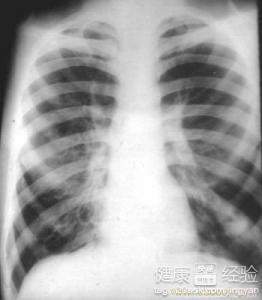

支氣管炎是一種常見(jiàn)的呼吸系統(tǒng)疾病,其癥狀包括咳嗽、咳痰、呼吸急促等,許多患者關(guān)心的問(wèn)題是:支氣管炎能自愈嗎?本文將詳細(xì)解析支氣管炎的類型、癥狀、治療方法以及能否自愈的問(wèn)題,幫助患者更好地了解并應(yīng)對(duì)這一疾病。

支氣管炎是指氣管、支氣管黏膜及其周圍組織的炎癥,根據(jù)其發(fā)病的急緩,可分為急性支氣管炎和慢性支氣管炎,急性支氣管炎通常由于病毒、細(xì)菌等感染引起,癥狀明顯且病程較短;而慢性支氣管炎則由于長(zhǎng)期吸煙、空氣污染等因素導(dǎo)致,癥狀持續(xù)較長(zhǎng)時(shí)間,易反復(fù)發(fā)作。